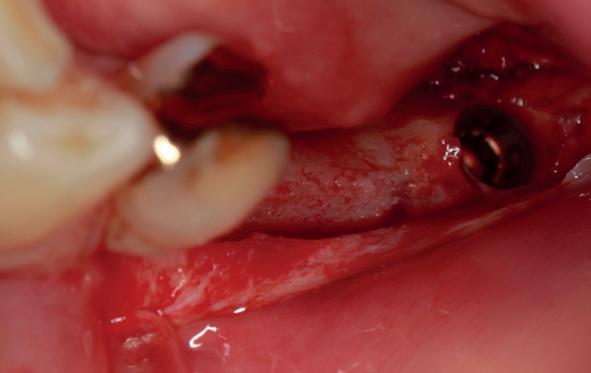

Vervaardigen essix retainer met dummies waarbij er een emergence profile van de 11 en 21 werd gevormd door eivormige dummies 4 mm in de gingiva te plaatsen

• Aanvulling zachte weefsels met de VISTA techniek en een vrij gingivatransplantaat uit het palatum links en direct dragen van de essix retainer

Na 4 weken intra-orale scan voor de etsbrug en kleurbepaling bij de technicus

14. Direct postoperatief plaatsen

van de essix met 2 dummy tanden

15. Twee weken post operatief

16. Creëren van een duidelijke indeuking in de mucosa voor emergence profile

18. Etsbrug frontbeeld

19. Etsbrug palatinaal